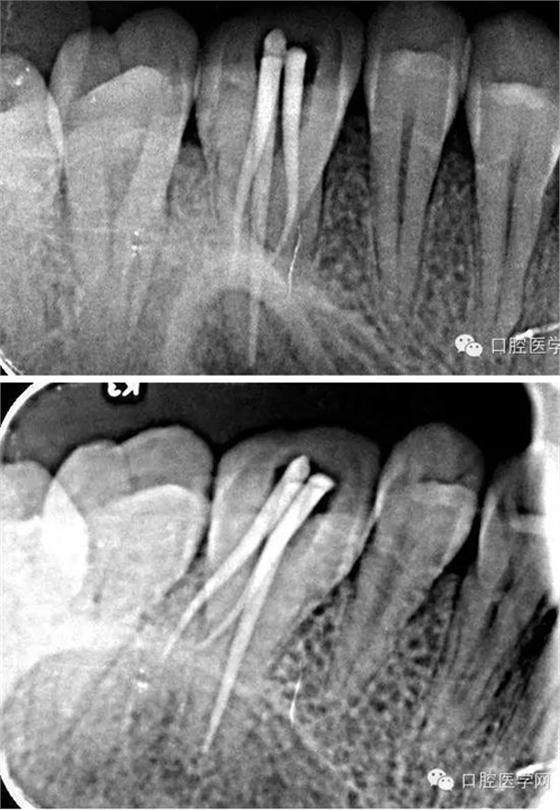

術(shù)中試尖x線片: